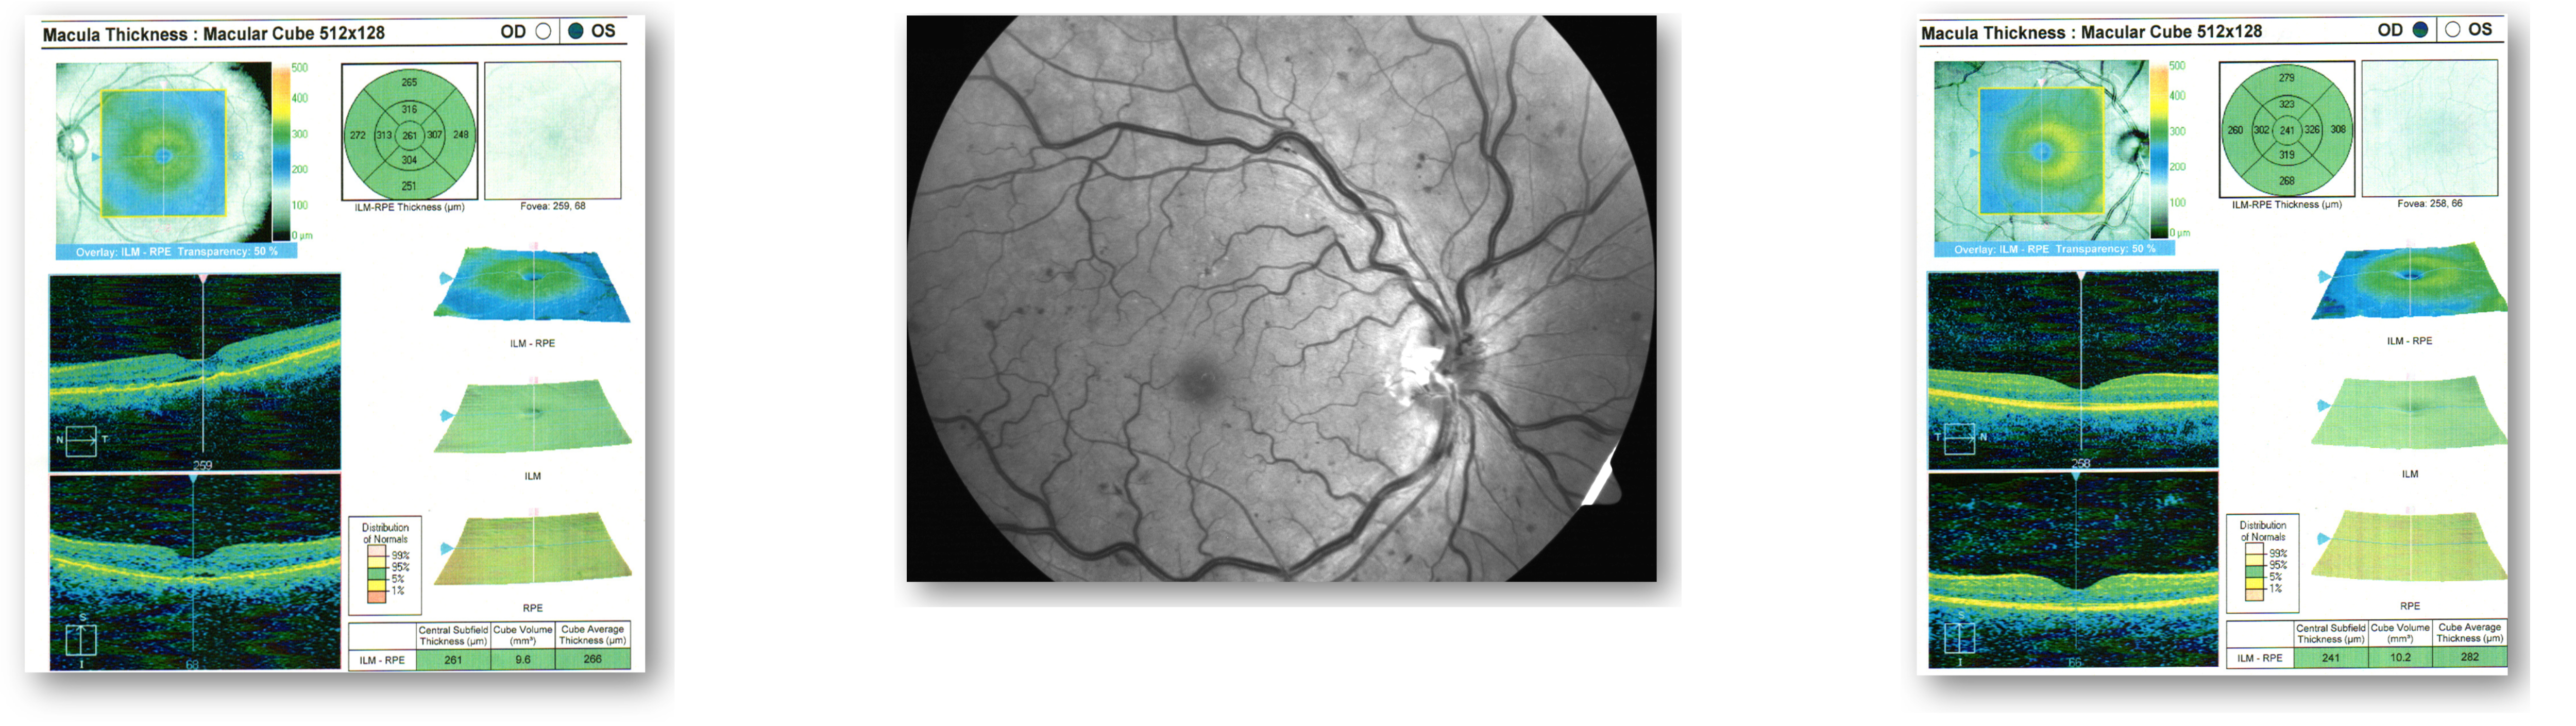

Figure 1 demonstrates what appears to be central serous retinopathy OS. Our typical management for this diagnosis is observation and follow-up in one month for a vision check and repeat OCT. The vast majority of these cases will resolve on their own within a month. Although there were no visual concerns OD, we also took photos and performed OCT on the right eye. Figure 2 shows what appears to be a healthy macula OD.

Figure 1: OCT and Fundus OS

Figure 2: OCT and Fundus